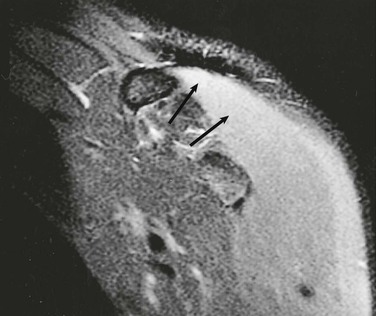

Denervation of a rotator cuff muscle can result from either a compressive neuropathy or an acute traumatic injury of a nerve. Compressive neuropathies most commonly result from a paralabral cyst associated with a labral tear, but they can also be caused by fractures or other masses in the area of the shoulder (see Fig. 44-23, A and C). Paralabral cysts (Fig. 44-28) most commonly arise in association with a SLAP tear or a posterior labral tear. These cysts may extend into either the suprascapular notch or the spinoglenoid notch and can result in entrapment of the suprascapular nerve, which innervates the supraspinatus and infraspinatus muscles.115 Paralabral cysts arising from an anteroinferior labral tear are less common, but they may compress the axillary nerve as it traverses the quadrilateral space.116 Compression of the axillary nerve can also result from adhesive bands in the quadrilateral space in athletes, such as pitchers, who participate in repetitive overhead activities.117 The axillary nerve innervates both the teres minor and deltoid muscles. Anterior dislocation can result in a stretching injury of the axillary nerve and give rise to a temporary or permanent denervation of the teres minor and deltoid muscles and can occasionally mimic a rotator cuff tear on clinical examination in a person with previous anterior dislocation. Denervation atrophy initially results in edema of the affected muscles and over time will progress to an irreversible fatty replacement. On MRI, acute denervation edema appears as a high T2-weighted signal within the affected muscle and is associated with reversible muscle atrophy (Fig. 44-29). The more chronic and irreversible form of fatty atrophy appears as decreased muscle bulk and bright streaks (representing the fat) within the muscles on T1-weighted images (see Fig. 44-23).